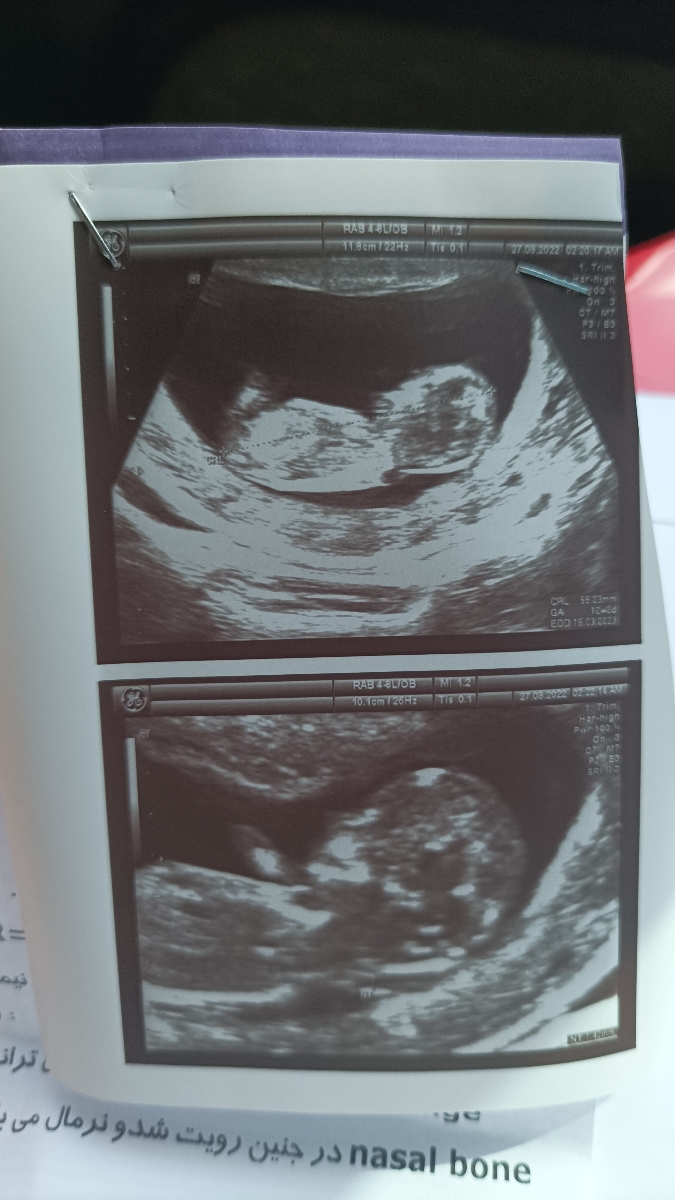

سلام خانم دکتر سونوی ان تی من سالمه؟جنسیت نشون داده میشه؟